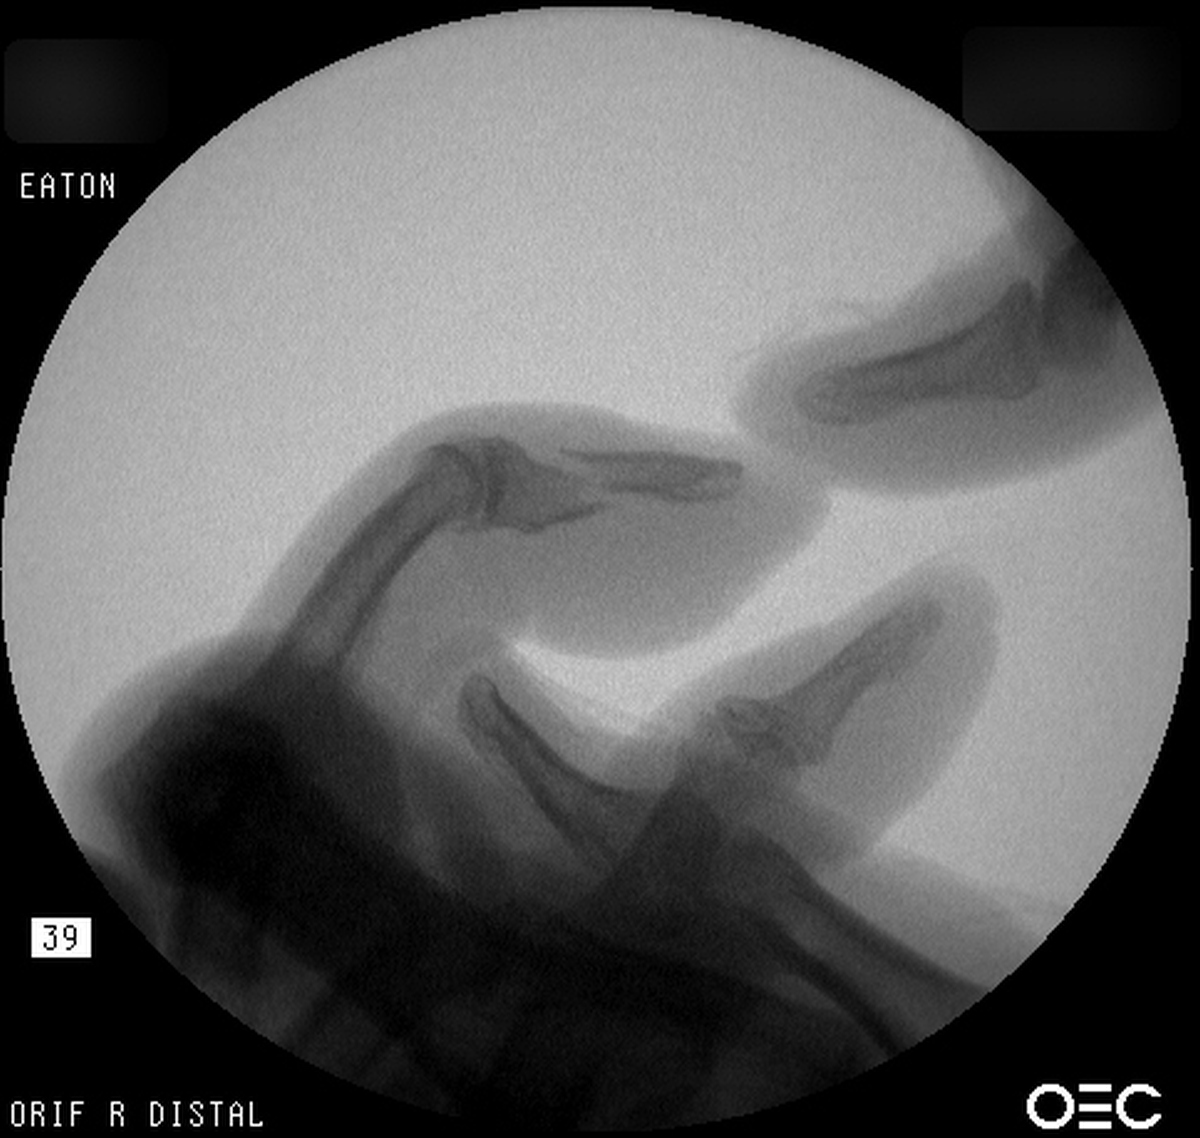

Case 5

Young man sustained bilateral metacarpal fractures.

The left hand injury included a small metacarpal base

comminuted fracture subluxation. |

| Percutaneous

fixation. |

| Thermoplastic

stabilization. |

| The right hand sustained a small metacarpal neck fracture with palmar angulation. |

| Reduction and

| Pin

| Pins were

removed at four weeks. Appearance at eight weeks

after surgery. |